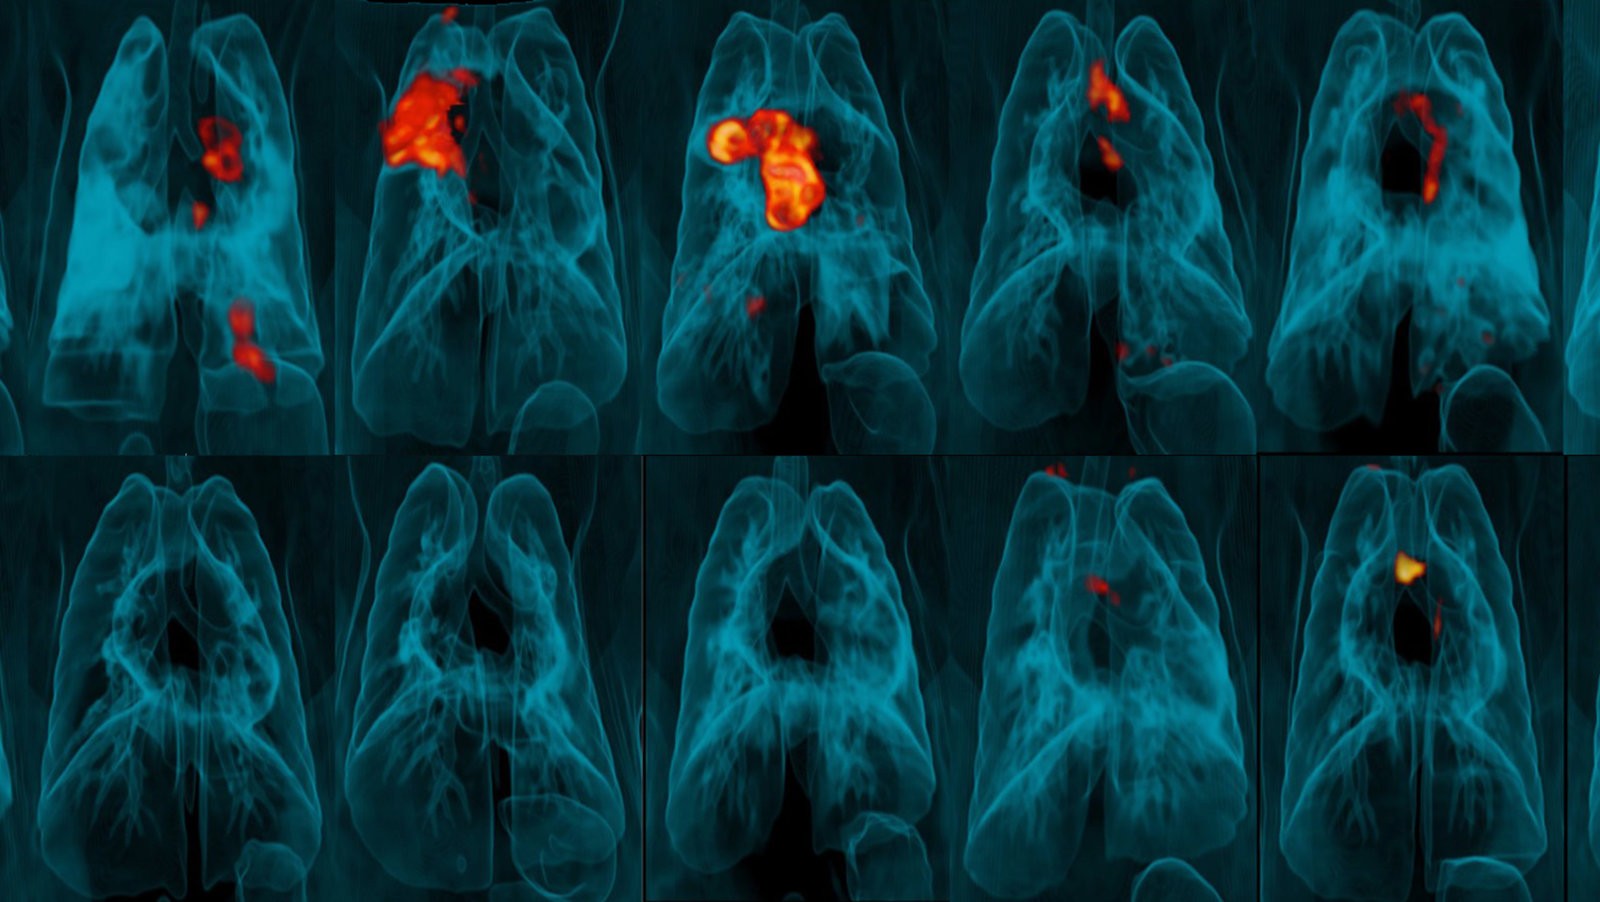

مرض السلّ أو الدرن أو التدرن والمعروف ب (بالإنجليزية: Tuberculosis) يُعرف بأنه مرض معدٍ بسبب العدوى البكتيربة التي يُصاب بها الشخص نتيجة العدوى ببكتيريا تسمى المايكوبكتيريوم، المتفطرة السلية، والتي تهاجم الجهاز التنفسي بشكل أساسي كالرئتين، وقد تصيب أجزاء أخرى بالجسم منها الكلى، الدماغ، والحبل الشوكي.

يُعدّ مرض السل أحد أنواع العدوى البكتيريّة المُعدية التي تؤثر بشكل أساسي في الرئتين، ولكنها قد تُصيب أيضاً أي جزء آخر في الجسم، كما ويعتبر هذا المرض أحد أكثر الأسباب المؤدية إلى الوفاه عالميّاً،ويتبع مرض الدرن نمطين معروفين عند إصابة الشخص به وهما:

وهي الحالة التي تظهر فيها الأعراض على المريض، والتي يمكن أن يبدأ بنقل المرض للآخرين فيها، وقد تحدث هذه الحالة خلال الأسابيع القليلة الأولى من الإصابة ببكتيريا السل أو أن تحدث بعد سنوات. أما أعراض السل النشط في حالة نشاط المرض، تهاجم بكتيريا السل الرئتين لتسبب ضررًا بالغًا في النسيج الرئوي ينتج عنه الأعراض الآتية : سعال مستمر لمدة ثلاثة أسابيع أو أكثر والذي قد يكون مصحوبًا بالدم. ألم الصدر والذي غالبًا ما يترافق مع التنفس أو الضحك أو السعال أو العطاس و فقدان الشهية والذي يتسبب بفقدان الوزن غير المخطط له في معظم الحالات و الحمى والتعرق الليلي والإرهاق والتعب العام و القشعريرة مع الشعور بالبرودة معظم الوقت.